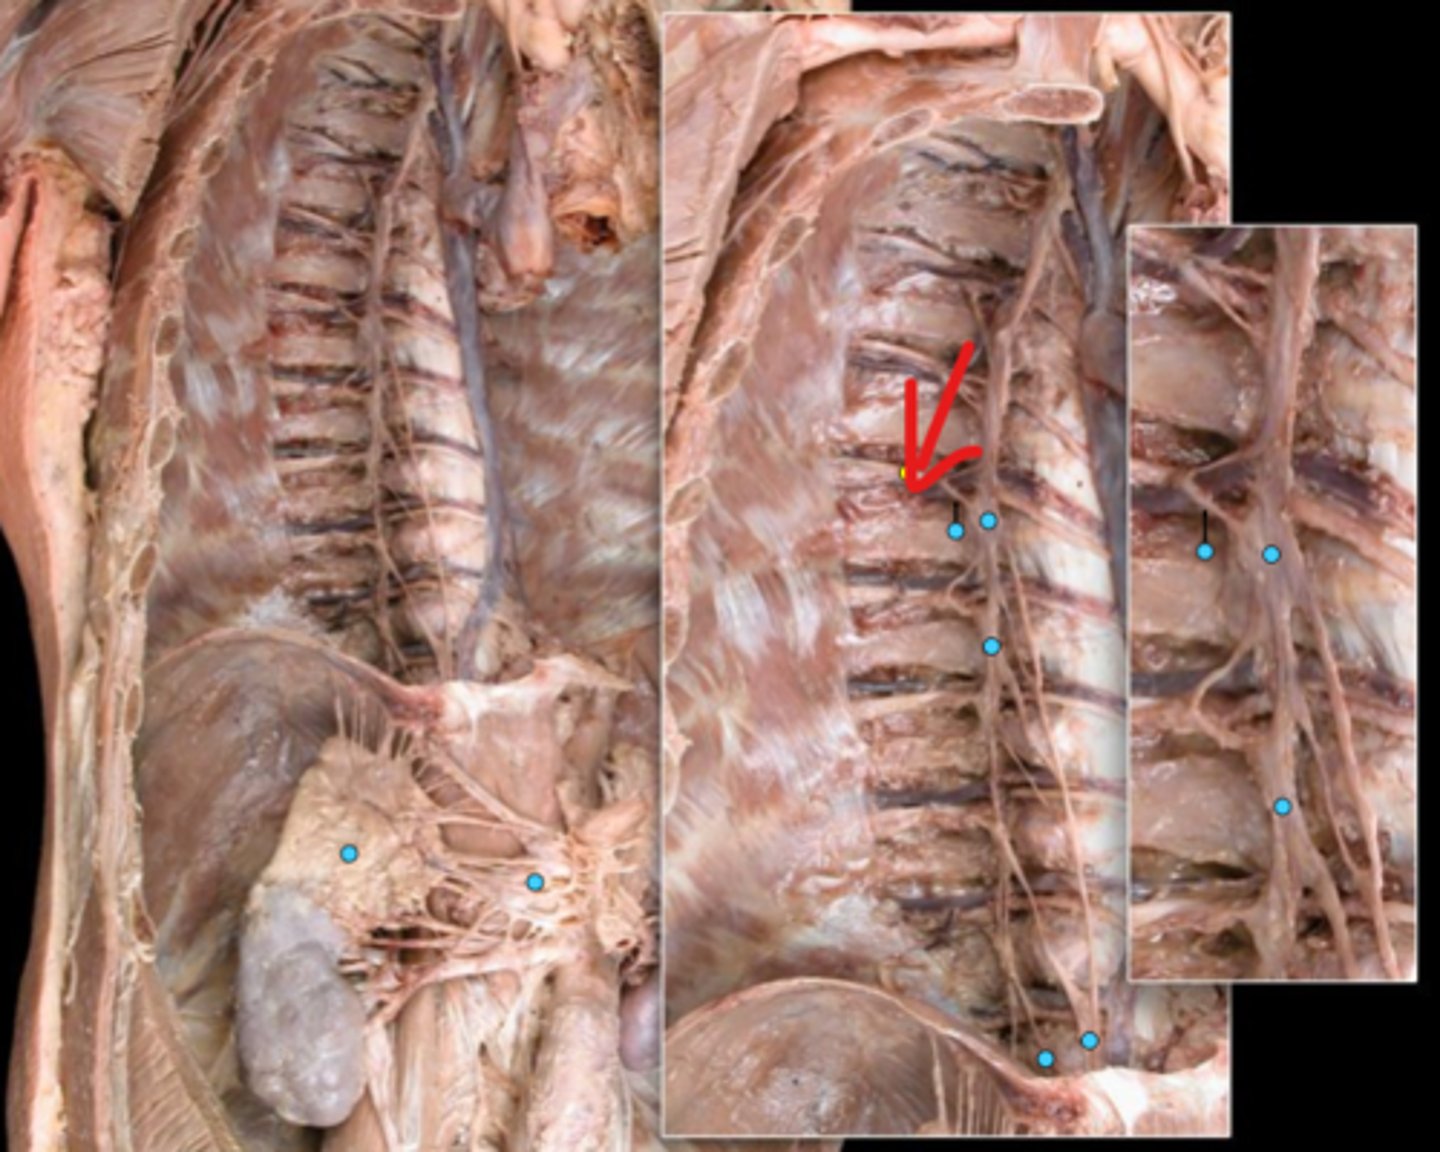

Suprarenal gland

Celiac ganglion

Intercostal nerve

Communicating ramus

Sympathetic trunk ganglion

Sympathetic trunk

Lesser splanchnic nerves

Greater splanchnic nerve

Anterior (ventral) ramus

Spinal nerve trunk

Posterior (dorsal) ramus

Spinal ganglion